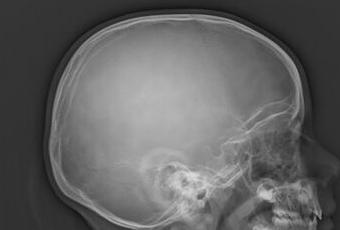

RADIOGRAFIA LATERAL DE CUELLO (VALORACIÓN AMÍGDALA)

HALLAZGOS:

-Estructuras óseas observadas de cráneo sin evidencia de lesiones líticas, blásticas o perdida de la contigüidad.

-Nasofaringe, adenoides, con un crecimiento aproximado mayor al 50% menor al 75%, dando una solución Grado 2.

OPINIÓN RADIOLÓGICA:

EL PRESENTE ESTUDIO RADIOGRAFICO CON HIPERTROFIA AMIGDALINA MODERADA (GRADO II).